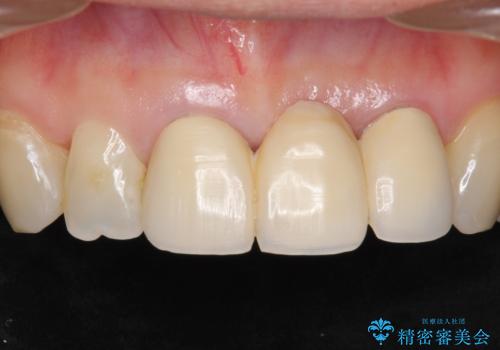

前歯のレジン前装冠(保険内)によるブリッジは、金属で裏打ちされており透明感がなく不自然で、ポンティックも必要以上に長く作られていました。

古いブリッジと金属の土台を除去し、ファイバーコア(金属を使わない強くてしなやかな土台)を植立したのち、オールセラミックのブリッジによる補綴治療を行いました。。